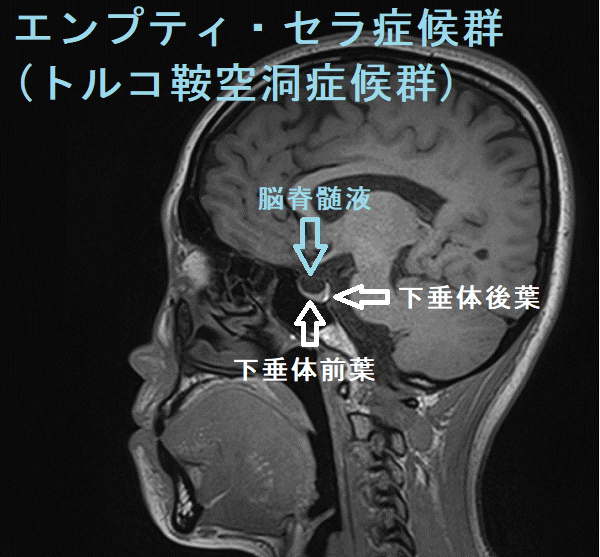

エンプティ・セラ症候群(empty sella症候群, トルコ鞍空洞症候群)は、クモ膜下腔がトルコ鞍内に下垂し、脳脊髄液で満たされた状態。原因は原発性、妊娠、自己免疫性下垂体炎、下垂体卒中、下垂体手術や放射線療法後。症状は視力障害、頭痛、脳脊髄液漏、下垂体機能低下症、中枢性甲状腺機能低下症[視床下部性(3次性)甲状腺機能低下症]、視床下部機能障害、高プロラクチン血症、先端巨大症、クッシング病、SITSH(TSH不適切分泌症候群)を引き起こす事も。原発性甲状腺機能低下症(橋本病・非橋本病)合併が多い。ダイナミックMRIで診断。治療は一般的に外科手術適応外。

エンプティ・セラ症候群(empty sella症候群, トルコ鞍空洞症候群)は、クモ膜下腔がトルコ鞍内に下垂し、トルコ鞍が脳脊髄液で満たされた状態です。

鞍隔膜の形成不全→トルコ鞍で髄液の拍動を強く受ける→くも膜下腔が下垂→下垂体が菲薄化